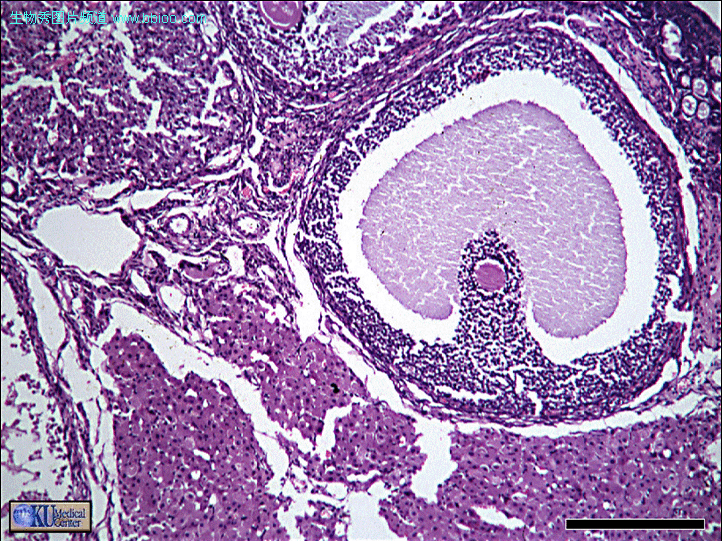

次级卵泡 近成熟卵泡

成熟卵泡